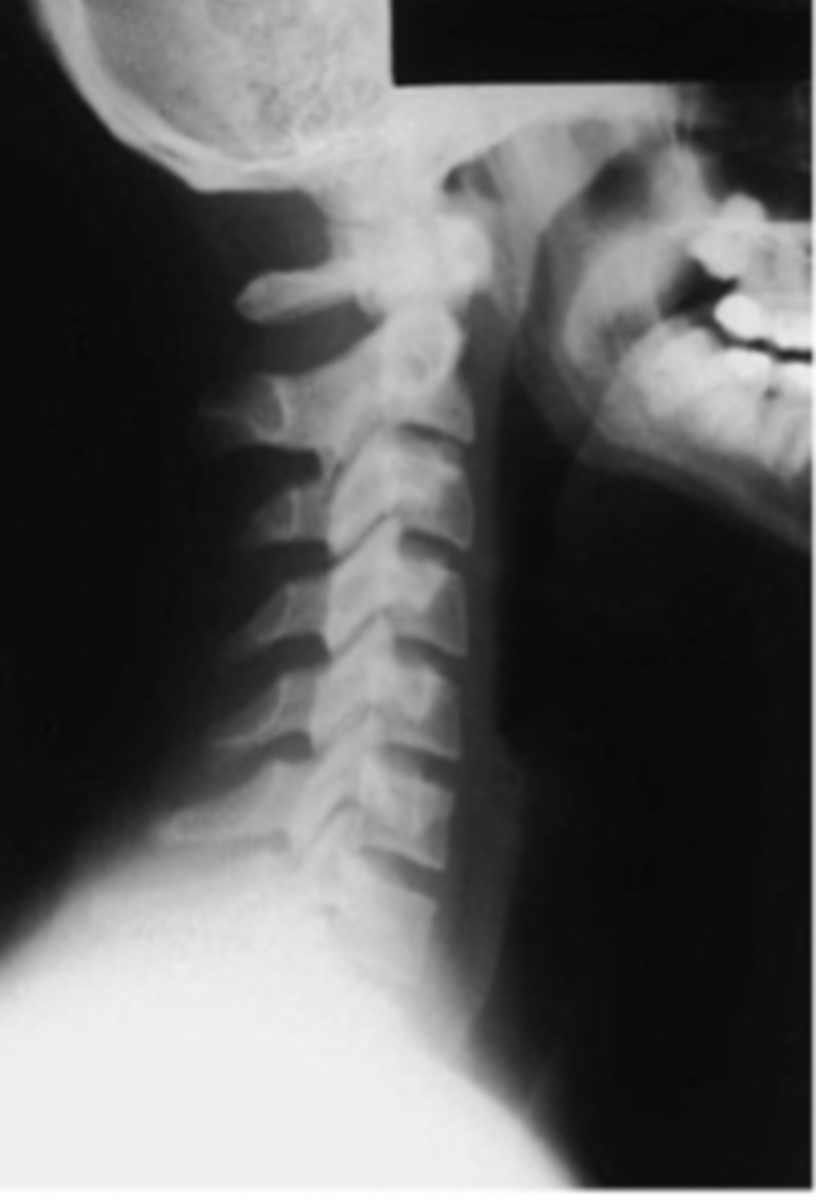

Oblique Cspine

What view is this?

Lateral Cspine